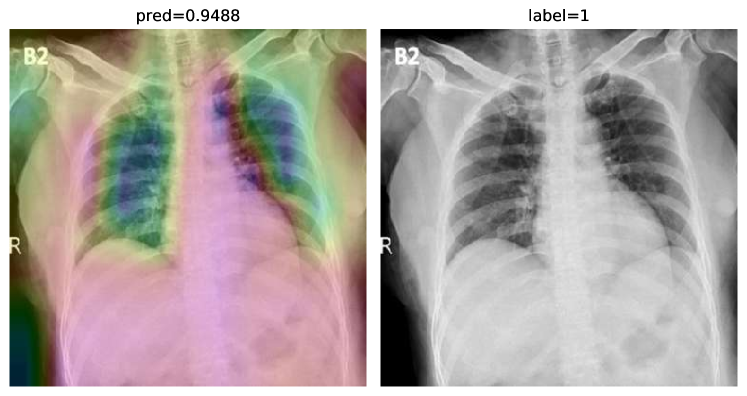

While text removal methods can prevent overfitting, we can simply force the model to look into the lungs in order to address both problems in one effort. To accomplish this task, a U-Net based segmentation illustrated in Fig. 4 is applied to the input images before enhancements. Visualization results for COVID-CXNet with the ROI-segmentation block are shown in Fig. 18.

Refer to caption

Figure 18: Grad-CAM visualization of the proposed model, trained with lung-segmented CXRs, over sample cases.

A figure with more Grad-CAMs is attached in Appendix B. From Fig. 18, it can be observed that COVID-CXNet with ROI-segmentation has delivered superior performance regarding the localization of pneumonia features. Worthwhile to mention that image augmentation is expanded by adding zoom-in, zoom-out, and brightness adjustment. Label smoothing is also applied to the loss function.

The proposed method has shown a negligible drop in metric scores; accuracy is decreased by 0.42%, and f-score is declined by 0.02. This decrease is a result of training with a larger dataset and accurately segmented ROIs, which means it has become more robust against unseen samples. There is a trade-off between catching good features and higher metric scores; while better features result in a more generalized model, high metric scores may indicate overfitting.